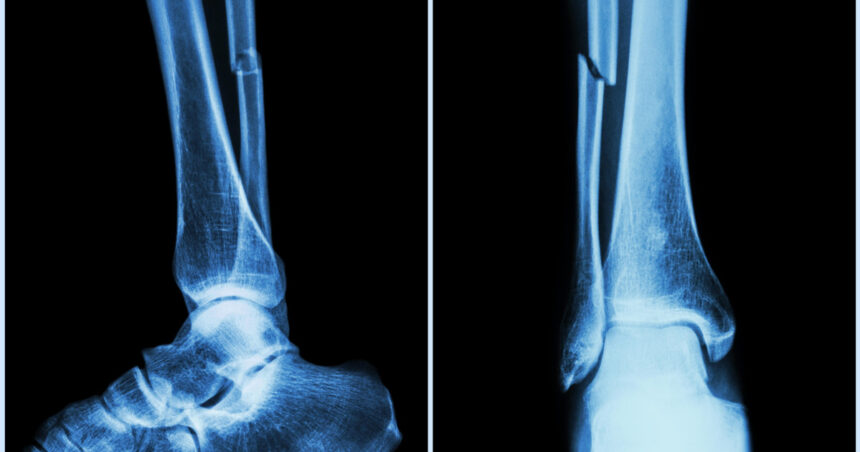

Cercetătorii din provincia Zhejiang, China, au dezvoltat un adeziv osos inovator, denumit „Bone-02”, care promite să transforme modul în care sunt tratate fracturile și fragmentele osoase zdrobite, printr-o procedură care durează doar trei minute. Această descoperire, condusă de dr. Lin Xianfeng de la spitalul Sir Run Run Shaw, ar putea reduce semnificativ necesitatea intervențiilor chirurgicale invazive și a implanturilor metalice.

În testele de laborator și în primele încercări clinice, „Bone-02” a demonstrat atât siguranță, cât și eficacitate. Procedura de aplicare a adezivului a fost finalizată în mai puțin de trei minute, comparativ cu metodele tradiționale care implică incizii mari și fixare cu plăci și șuruburi metalice. Formula adezivului combină compuși de calciu și proteine specifice, asigurând o legătură puternică, flexibilă și sigură. Aplicarea sa necesită doar o incizie minimă, prin care adezivul este introdus direct în zona fracturată, sigilând fragmentele osoase rapid.